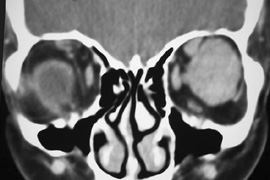

Fig. 6. Lateral orbitotomy through upper eyelid skin crease A. Photo demonstrating right globe ptosis present for more than 2 years. B. Axial CT scan showing a well outlined oval lesion in the lacrimal gland

fossa. C. Coronal CT showing lesion pushing globe inferiorly. D. Skin crease excision marked for lateral orbitotomy. E. Lateral orbital rim exposed. Bone cuts made above frontozygomatic suture

and at zygomatic arch. F. Lateral wall removed. Subperiosteal space exposed. Hard tumor could be

palpated in area of lacrimal gland. G. Benign mixed tumor of lacrimal gland removed. H. Bone sutured into place. I. Skin crease closed. |